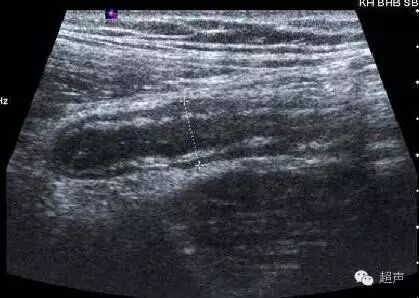

急性坏疽性阑尾炎:

阑尾管壁连续性中断。边界模糊呈不规则实块状,可见粪石,内见散在光点,周边可见较多渗出性无回声区。阑尾及周围组织无血流信号。